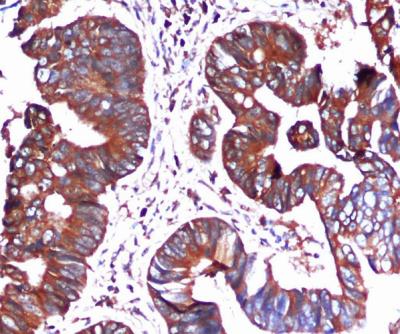

- Immunohistochemistry analysis of paraffin-embedded Colorectal cancer using BiP/GRP78 (Cterminus) antibody. High-pressure and temperature Sodium Citrate pH 6.0 was used for antigen retrieval.